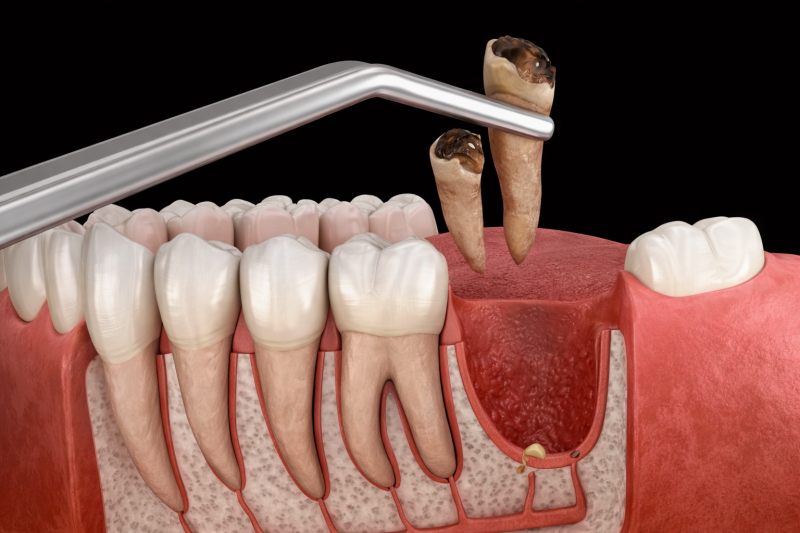

Extraction dentaire suite problème infectieux

Extraction (avulsion) dentaire avant la pose d’un implant

Lorsqu’aucune de nos thérapeutiques ne permet de restaurer une dent de manière stable et pérenne, ou que sa présence en bouche est un risque pour votre état de santé général, nous avons recours à l’...